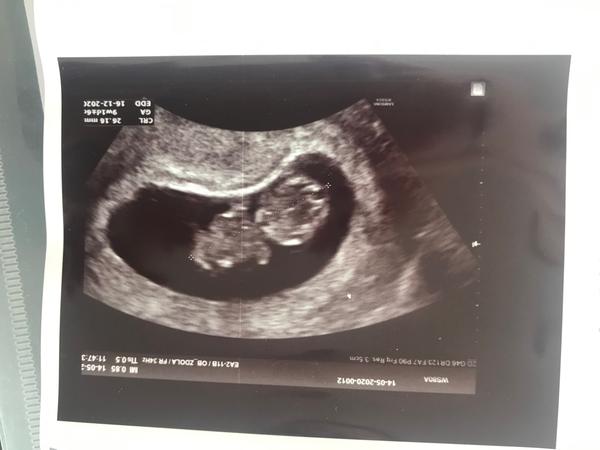

@marta_kovar Tak to leda ty, když si vybavíš co kde bylo... tam jde i o natočení... prostě co je hlavička a co zbytek tělíčka z toho moc nerozšifruješ, ale i tak je to pěkný ne? 😉 Já mám u všech dětí taky nejdřív tohle a pak už pěkné mimozemšťánky ( jeden vypadal i jako žabka 😀 )

@marta_kovar Jeste par tydnu bude vypadat jako mimozemstanek, ale pak uz to zacne vic cloveka pripominat. Krasny je uz ted, vid?

@michaela2609 Ano, už z 10 tt je vidět hezky kde co má. Takže už jsem v klidu. 😅